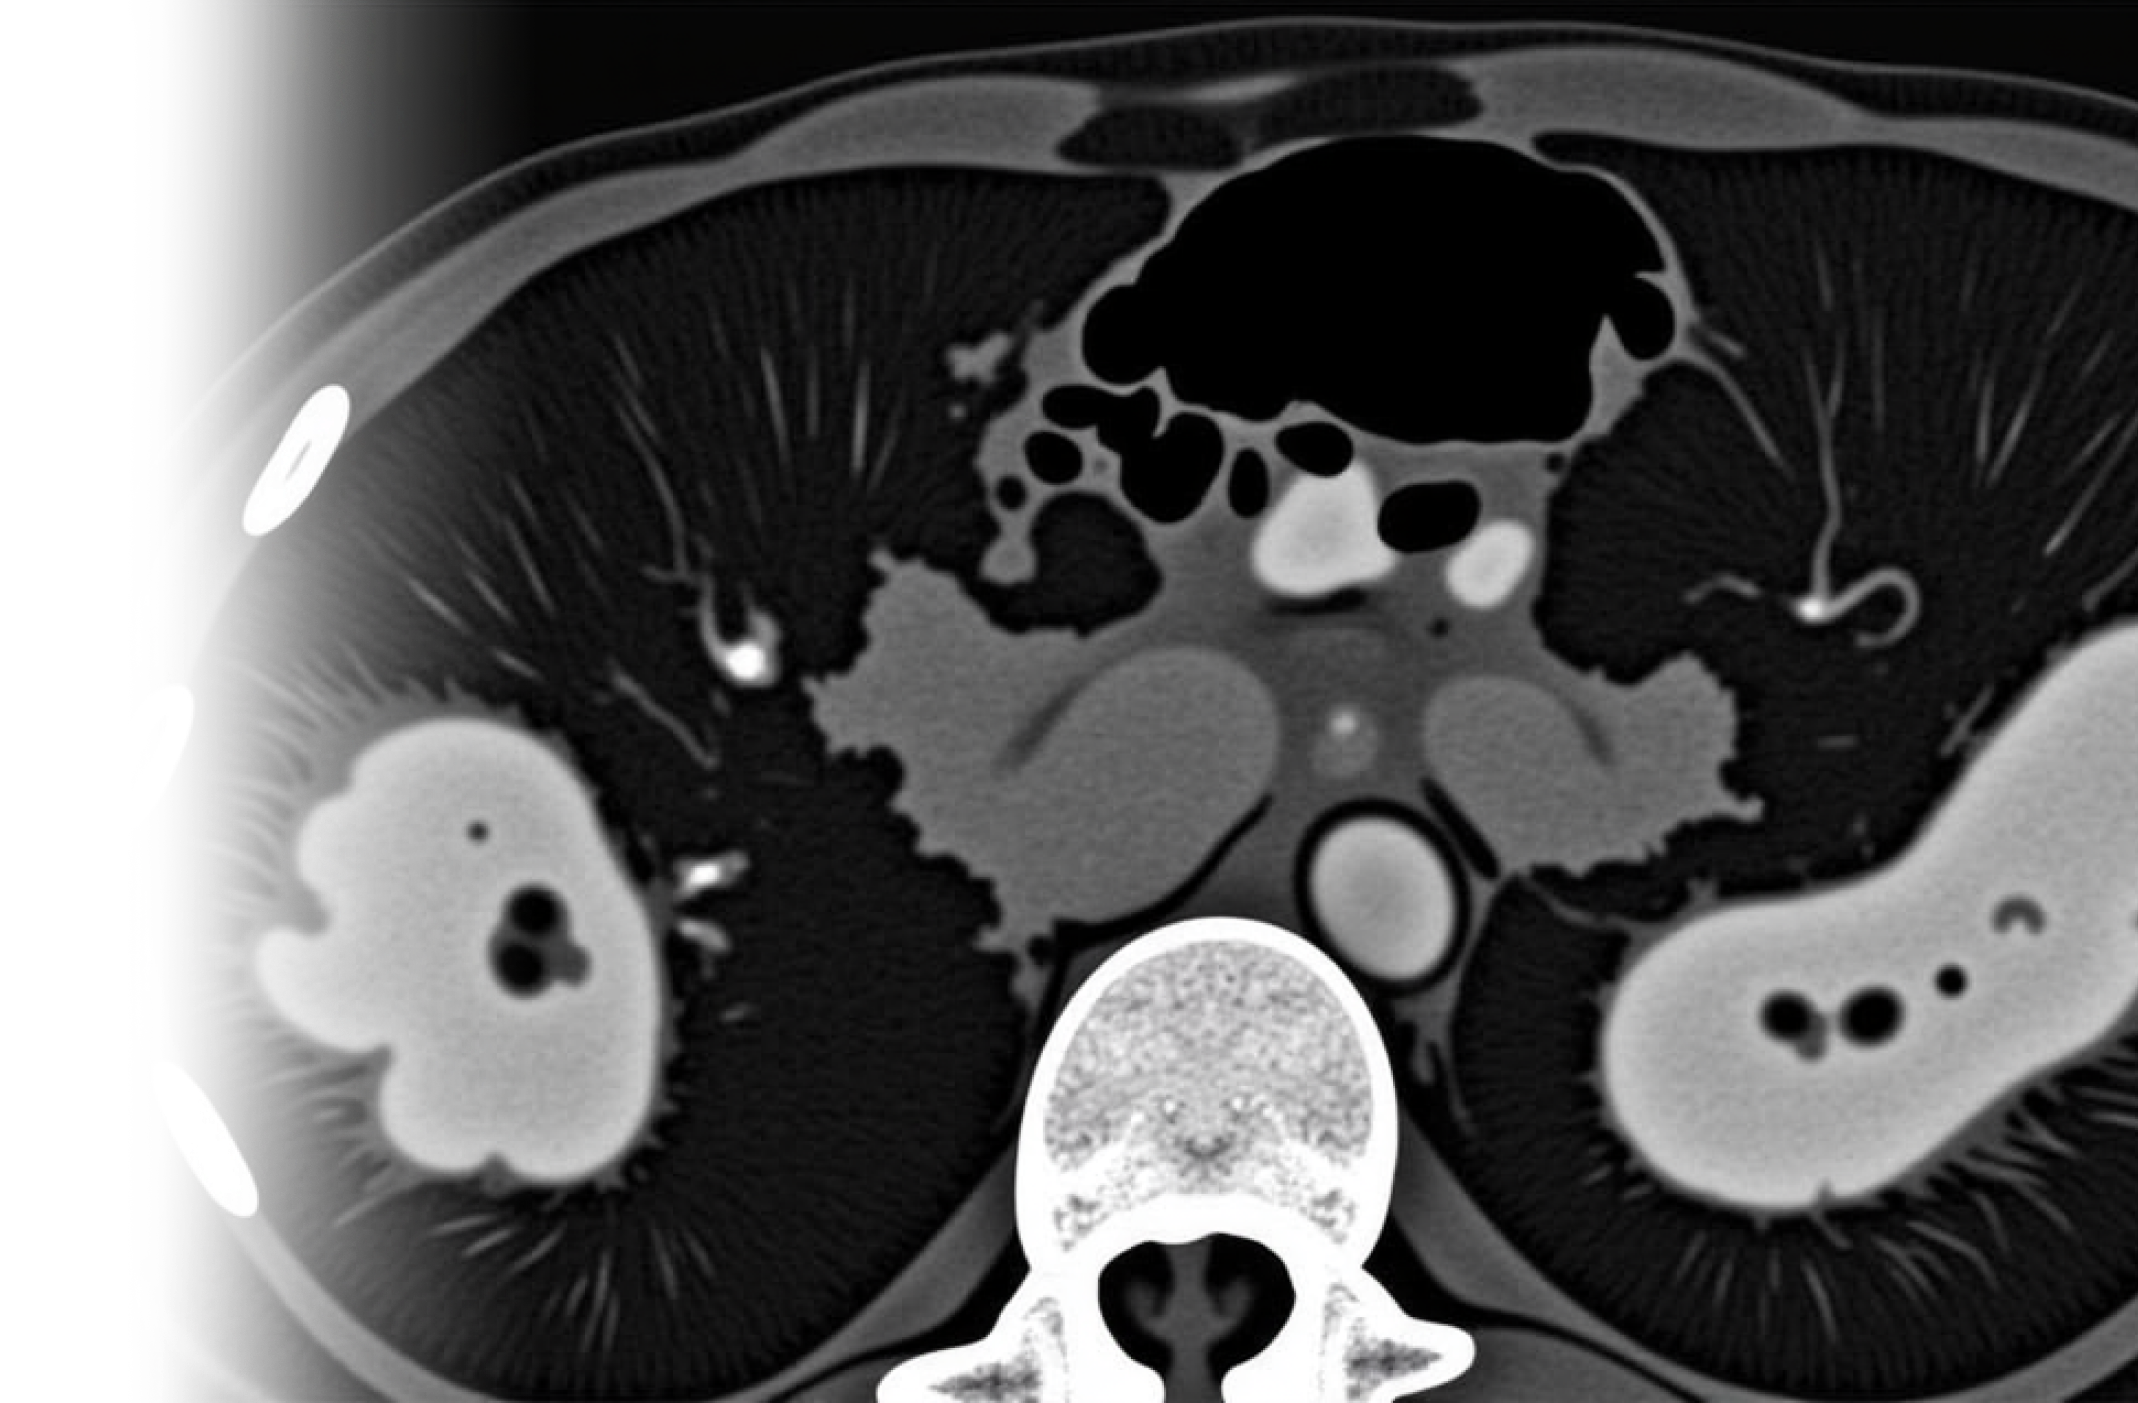

Компьютерная томография органов грудной клетки, брюшной полости и забрюшинного пространства с контрастированием – важный метод исследования органов грудной клетки, брюшной полости с внутривенным введением йодного контрастного препарата с помощью автоматического инжектора и с последующим пофазным сканированием.

Пациенту внутривенно вводится контрастное вещество, которое обеспечивает более качественную видимость органов на получаемых снимках, что позволяет выявить даже самые незначительные изменения в исследуемой области.

высококачественные снимки органов и тканей